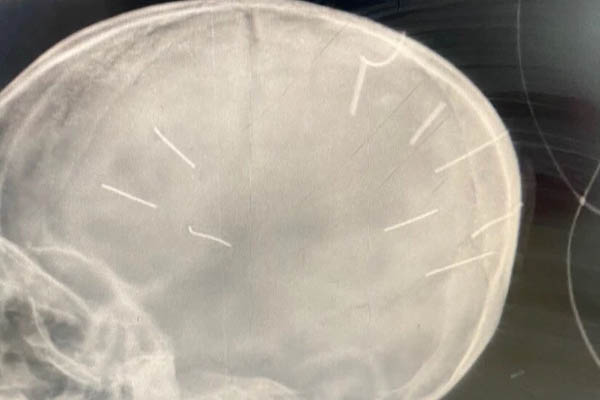

Tại đây, sau khi tiến hành chụp X-Quang, các bác sĩ Bệnh viện Đa khoa huyện Thạch Thất phát hiện trên sọ bé A. có nhiều vật thể giống đinh găm bên trong, tổng cộng 9 chiếc, trên đầu có chút sưng tấy.

9 vật giống đinh găm vào sọ bé A.